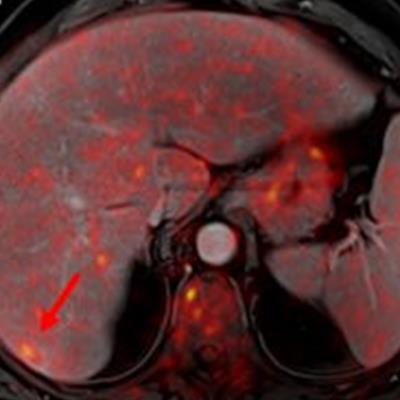

Indeterminate lesion on PET/CT classified by PET/MRI for 53-year-old man with lung cancer. Contrast-enhanced CT (A), PET (B), and fused F-18 FDG PET/CT (C) images are displayed in comparison with contrast-enhanced T1-weighted MRI (D), PET (E), and fused F-18 FDG PET/MRI (F) images. In CT (A), hyperdense, subcentimeter liver lesion (arrows) in segment VII is suggestive of transient hepatic attenuation difference or small hemangioma. As malignancy cannot be excluded, it needs further investigation. On PET/MRI, lesion is clearly classified as metastasis because of contrast enhancement and tracer uptake due to later acquisition time point. Follow-up CT confirmed diagnosis after 78 days. Image courtesy of the Journal of Nuclear Medicine.

Indeterminate lesion on PET/CT classified by PET/MRI for 53-year-old man with lung cancer. Contrast-enhanced CT (A), PET (B), and fused F-18 FDG PET/CT (C) images are displayed in comparison with contrast-enhanced T1-weighted MRI (D), PET (E), and fused F-18 FDG PET/MRI (F) images. In CT (A), hyperdense, subcentimeter liver lesion (arrows) in segment VII is suggestive of transient hepatic attenuation difference or small hemangioma. As malignancy cannot be excluded, it needs further investigation. On PET/MRI, lesion is clearly classified as metastasis because of contrast enhancement and tracer uptake due to later acquisition time point. Follow-up CT confirmed diagnosis after 78 days. Image courtesy of the Journal of Nuclear Medicine.After exclusions, the researchers examined 1,003 PET/MRI scans of 918 patients. PET/MRI outperformed PET/CT in terms of providing more tumor information (26.3%), mostly in patients with malignant bone disease, followed by lung cancer, prostate cancer, and gynecologic or breast cancer. PET/MRI identified additional malignant findings in 5.3% of cases, which lead to a change in tumor, node, and metastases (TNM) staging in 2.9% of cases. PET/MRI also clearly classified indeterminate PET/CT lesions in 11% of cases.